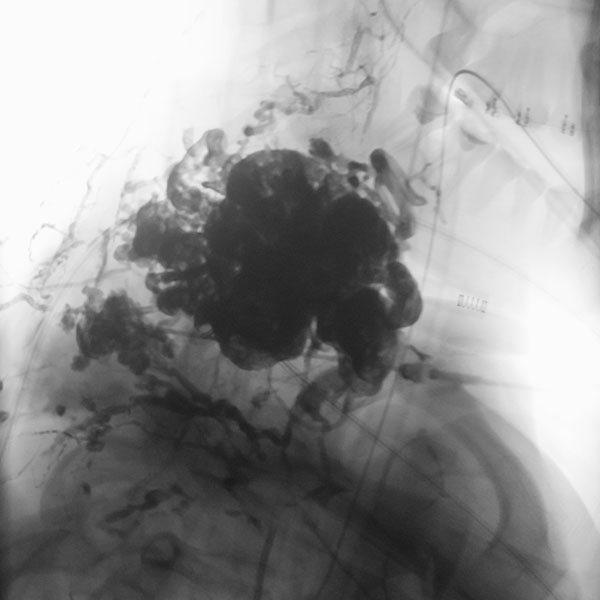

Digitale Subtraktionsangiographie (DSA), Nativbild. Der Nidus der arteriovenösen Malformation wurde jetzt in 2 Sitzungen sukzessive nach direkter Punktion mit einer Nadel mit dem flüssigen, zäh wie Lava fließenden Embolisat Ethylen-Vinyl-Alkohol-Kopolymer (EVOH) aufgefüllt im Sinne einer Embolisation. Der Nidus ist am Ende nach Injektion von 37 Ampullen des röntgendichten Embolisats komplett aufgefüllt. Es kommt zu keinem Durchstrom mehr, die arteriovenöse Malformation ist verschlossen.

Digitale Subtraktionsangiographie (DSA) mit proximaler Injektion in die linke A. subklavia mit Darstellung der A. vertebralis nach Abschluss der 2. Embolisation. In dieser späten Phase nach Injektion stellen sich zwar noch einige arterielle Feeder dar, diese finden jedoch keinen Anschluss mehr an den Nidus der arteriovenösen Malformation. Auch zeigt sich kein venöser Abstrom mehr. Damit ist die AVM verschlossen.